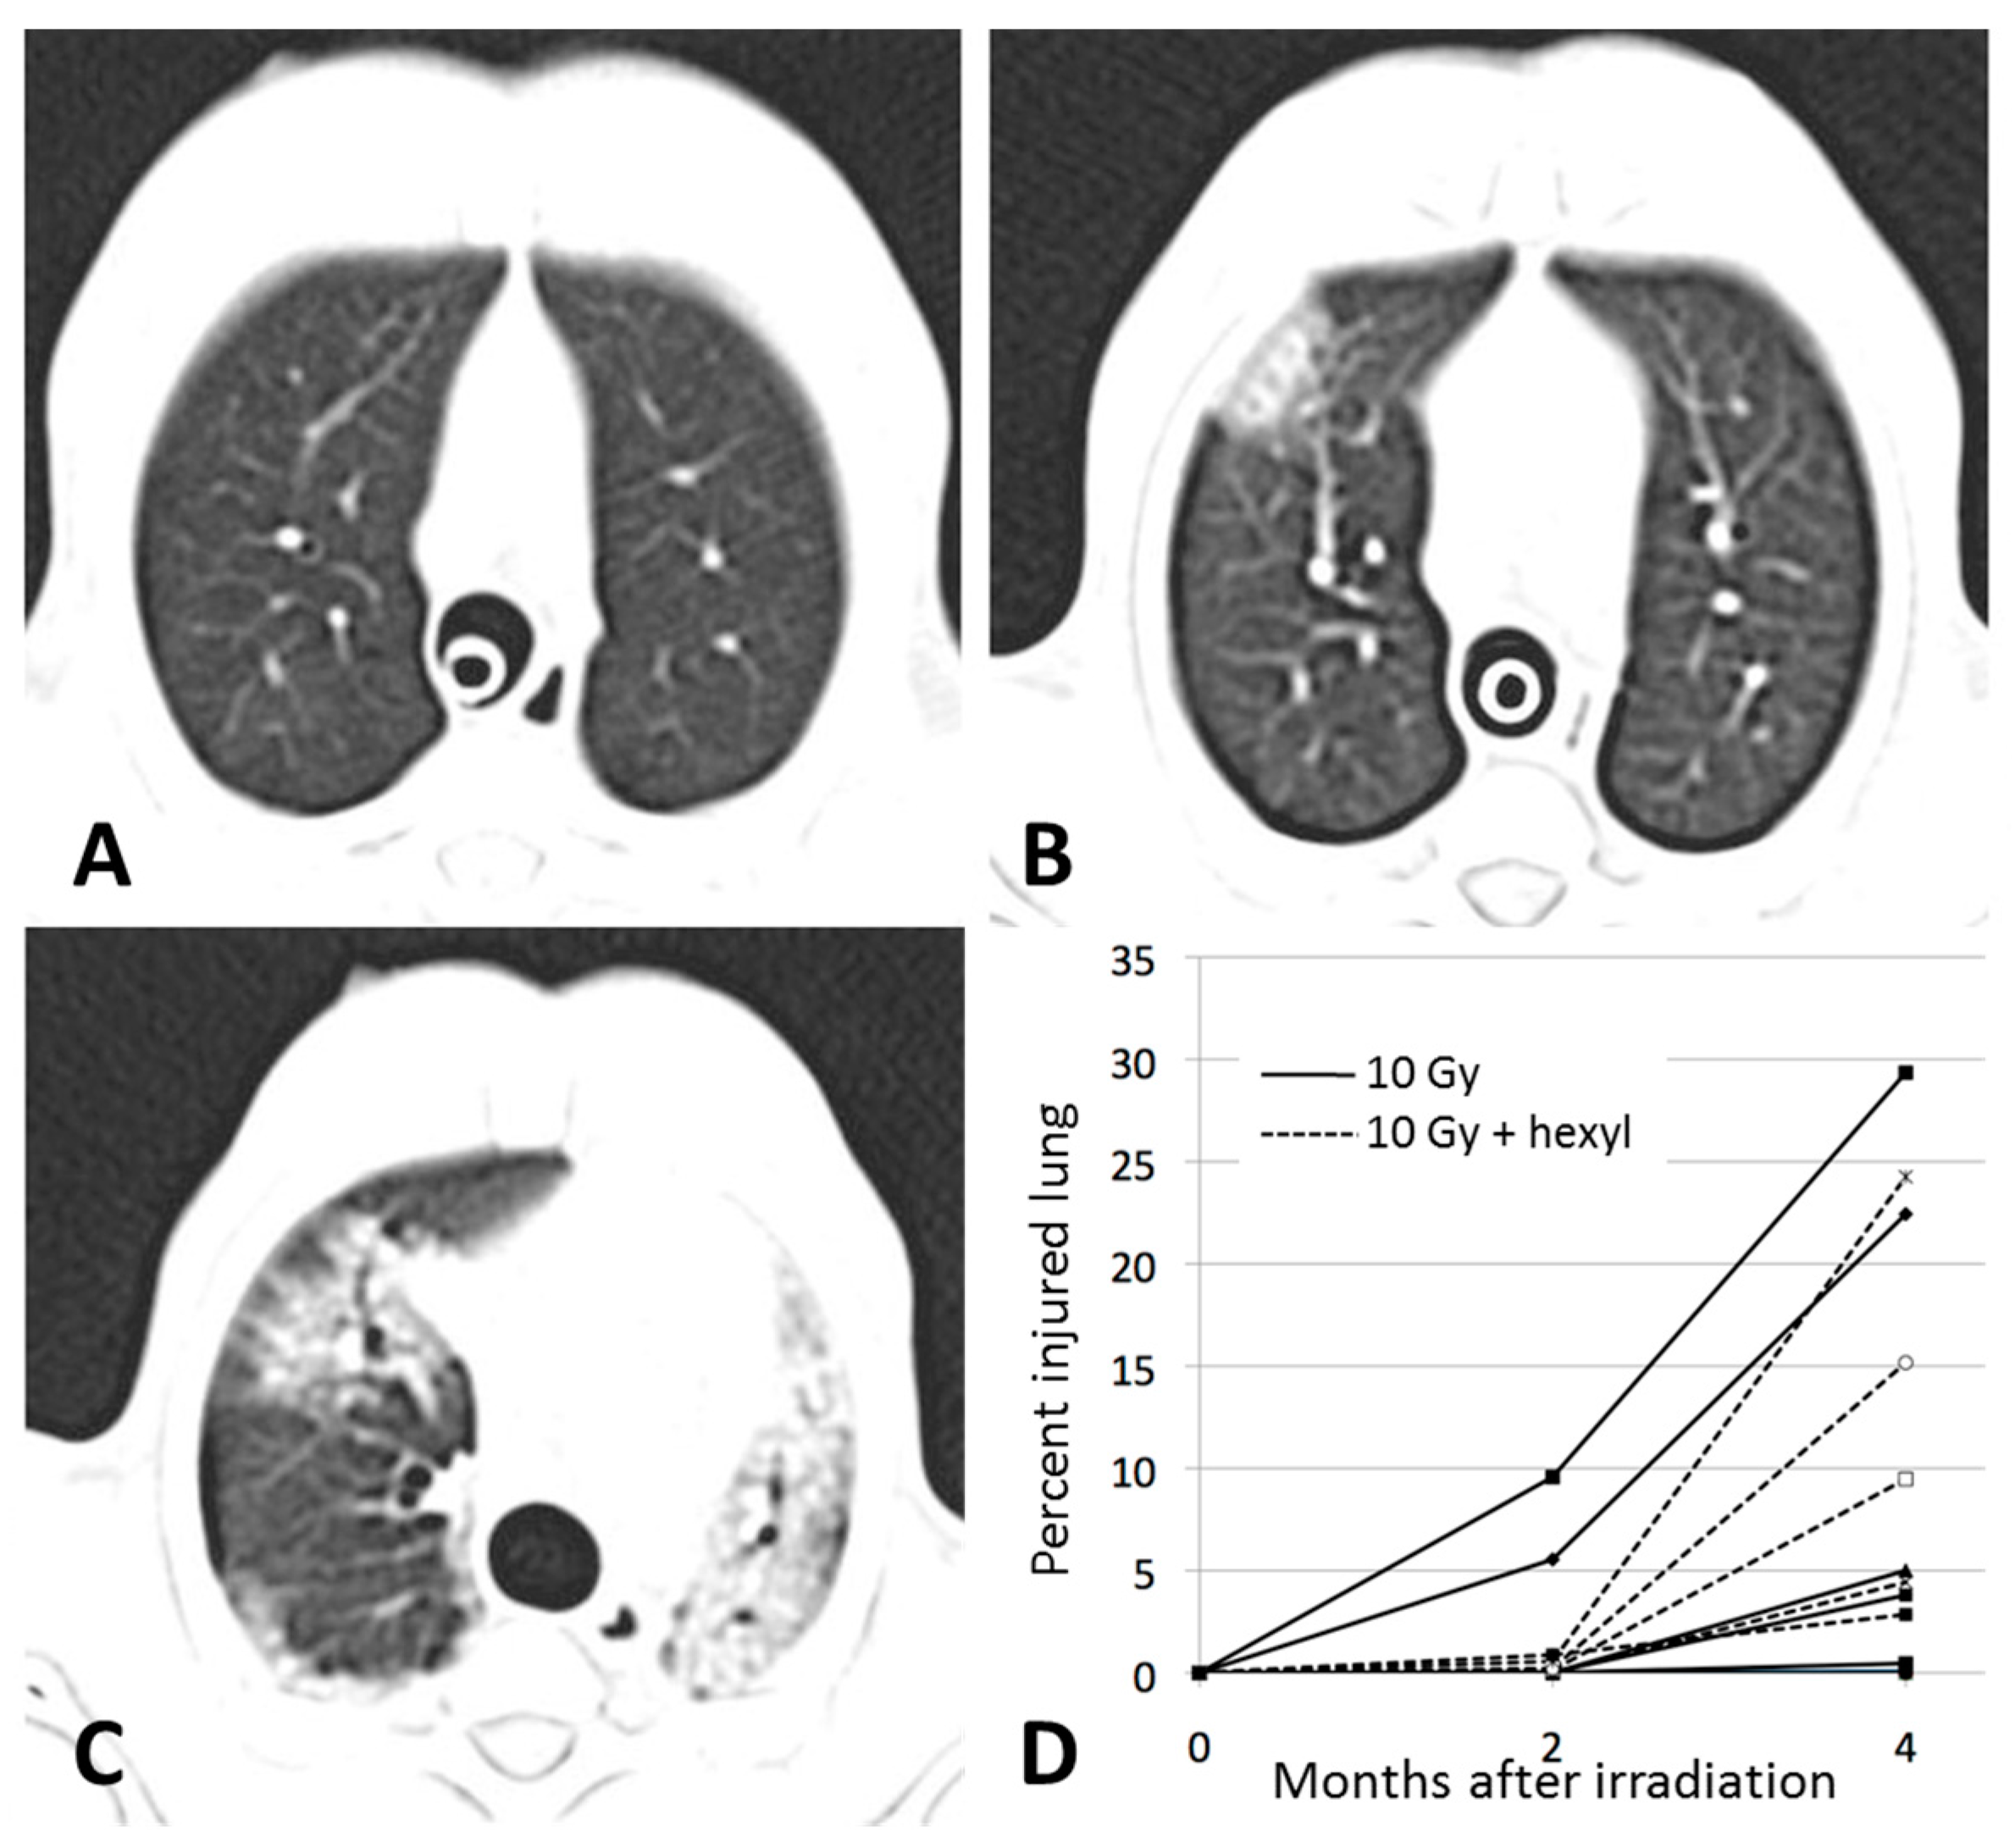

2.4. Computed Tomography Imaging

3.3. CT Imaging